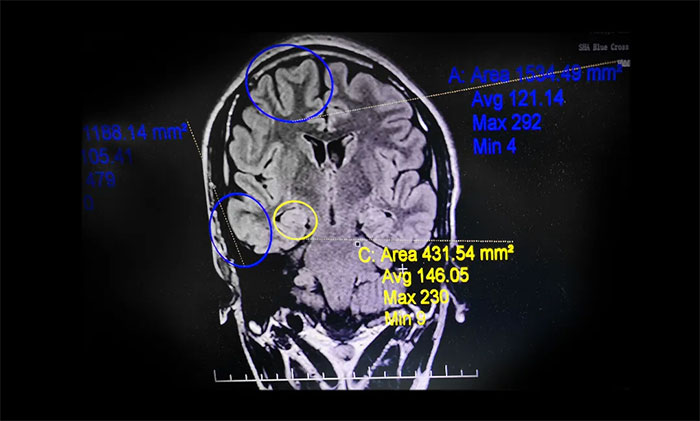

▲ 系列檢查,明確患者致癲灶

小楊病情困擾一家人多年,父母要求手術(shù)治療的意愿強(qiáng)烈。楊忠旭教授團(tuán)隊(duì)經(jīng)過全面細(xì)致的檢查和詳細(xì)的術(shù)前評(píng)估,最終明確患者致癲灶,且手術(shù)指征明確,未見明顯手術(shù)禁忌癥。